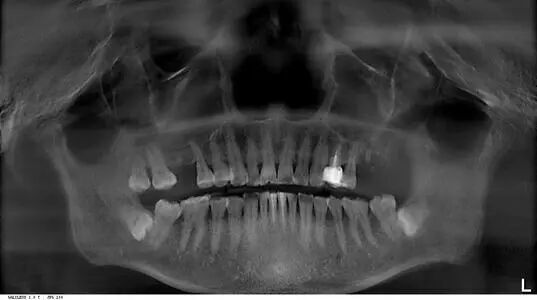

口腔全景片可以看到种植牙嘛?

答:可以的!种植牙等修复体在口腔全景片上展现的通常是白色的,可以很清晰的看出来,比如下图中就有1颗种植牙。

曲面断层片怎么看科普知识:你会看牙片嘛?今天手把手教你看!_https://www.jmylbn.com_新闻资讯_第15张